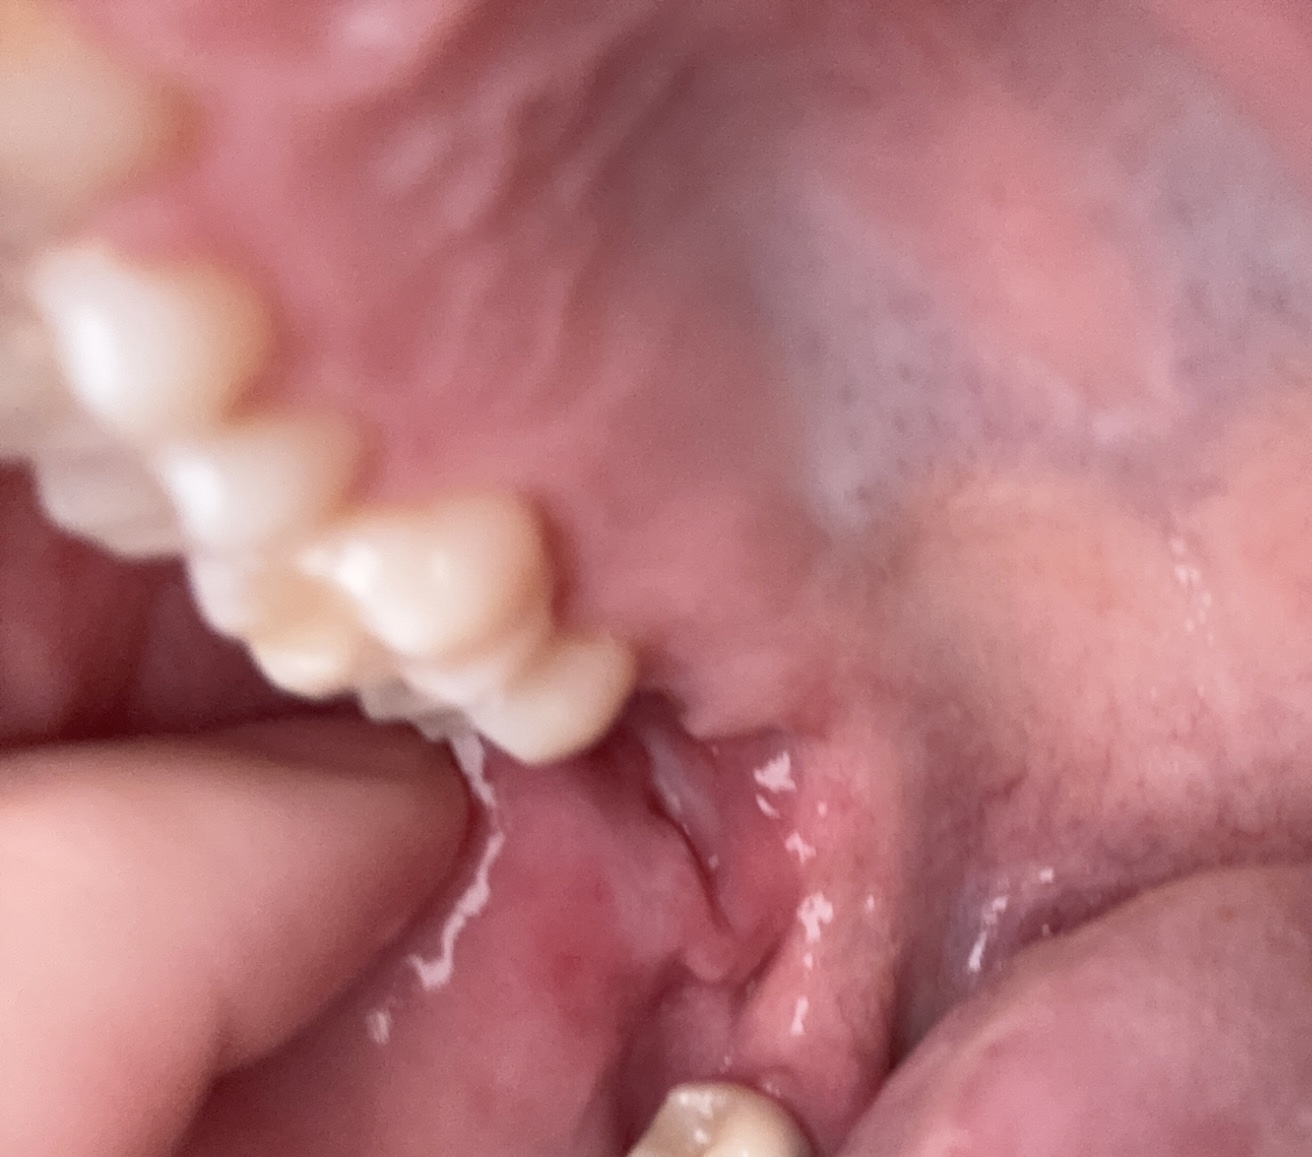

Author: helpikbenbang Posted: ma, 10/27/2025 - 18:00 Tot mijn grote schrik kwam ik dit tegen achter in mijn mond. Ik ben hartstikke bang dat het foute boel is. Zijn er tandartsen die vaker dit ‘zwellingen’ zien? helpikbenbang Foto bijgevoegd Foto bijgevoegd Stuur privébericht Attach Login of registreer om te reageren ma, 10/27/2025 - 18:07 Permalink Tandarts_Richa… Eerst kijken waar het door… Eerst kijken waar het door komt. Zijn de verstandkiezen er nog. X- Foto laten maken. Maandag afspraak maken. Stuur privébericht Login of registreer om te reageren ma, 10/27/2025 - 23:53 Permalink 88 weergaves

Tandarts_Richa… Eerst kijken waar het door… Eerst kijken waar het door komt. Zijn de verstandkiezen er nog. X- Foto laten maken. Maandag afspraak maken. Stuur privébericht Login of registreer om te reageren ma, 10/27/2025 - 23:53 Permalink